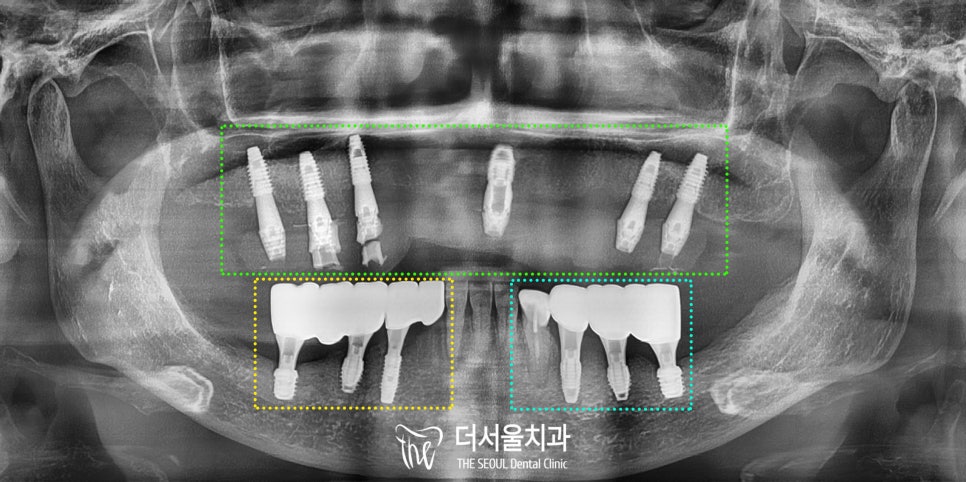

3. 디지털 풀아치 전체 임플란트

4~6개의 디지털 임플란트를 식립하고,

잇몸뼈와 인공치아를 연결하는 방법으로

최소 식립으로 전체 치아의 기능을

살릴 수 있습니다.

“풀아치 = Full Arch”

말 그대로 전체에 고르게 아치 모양대로

균형을 맞춰 식립하여 고정력을 얻으니

내 치아와 같은 편안함을 얻을 수 있습니다.

성남 치과의원의 수술 가이드를 통해

정확한 픽스처의 위치를 잡으면서

진행된 모습입니다.

(사실 하악도 함께 진행하였는데

오늘 포스팅에서는

상악을 위주로 설명드리겠습니다.)